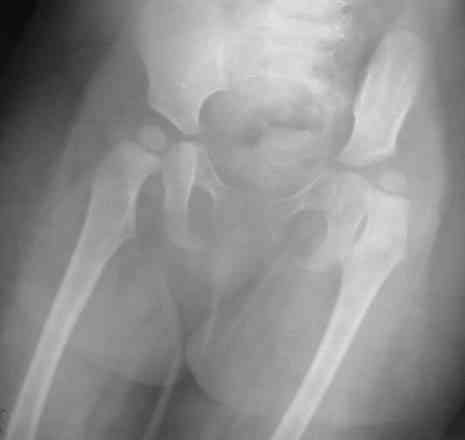

Уважаемые коллеги!Окажите, пожалуйста, консультативную помощь! Девочка, 1 г 9 мДЗ: врожденная патология головного мозга, врожденная дисплазия, подвывих, приводящая контрактура левого тазобедренного сустава, микроцефалия, миоклонические припадки, грубая задержка психофизического развития, с-м Айкарди?

Особенности объективного осмотра в настоящее время:Умеренный тетрапарез. Признаки рахита (деформация костей черепа, четки). Дыхание пуэрильное. Тоны сердца ритмичные, шумов нет. Живот мягкий, безболезненный, печень +1,5 см. Склонность к запорам. Местный статус: резкое приведение левого бедра, относительное укорочение левой нижней конечности. Ограничение отведения в тазобедренных суставах, особенно слева. Гипертонус мышц левой нижней конечности. Ограничение сгибания в левом коленном суставе.

Объем движений (левый ТБС): сгибание-разгибание (фиксированное) 65-165; разведение - D 45, S 65. Положение сустава по отношению к линии Розера-Нелатона - D 0,5 см, S 1,5 см. Хронаксиметрия - возбудимость нервных стволов нижних конечностей в норме, двигательная реакция мышц типичная.

Hi, this is pretty typical windblown hip deformity: abduction on rt side, adduction on the lt(according to your anamnesis kind of CP. Lt side already subluxated , no treatment will lead to further dislocation.I think that best way for treatmen now is : adductor tenotomy on the lt + spica cast ( 50-60 degrees abduction with wood bar between legs), after 6 weeks change to another 6 weeks; than for 6 months night plastic abduction brace.